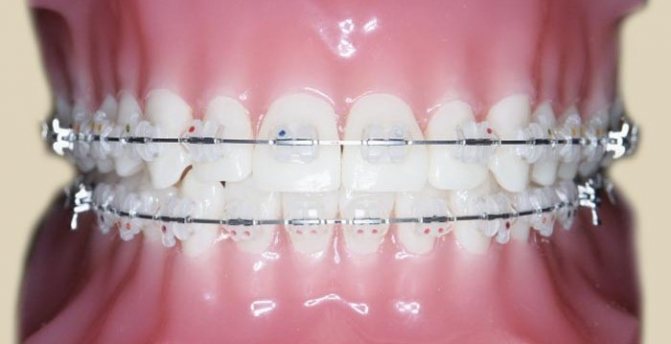

- Двухчелюстное. Используется при самых сложных травмах, когда повреждены обе челюсти, часто со смещением, поврежденными отломками. Накладывается шина Тигерштедта, при которой конструкция из медной проволоки закрепляется на здоровых зубах. Между собой они смыкаются резиновыми кольцами, крючками. Подвижные зубы в зависимости от их состояния удаляются или включаются в конструкцию с помощью отверстий в кости.

Сегодня существуют современные аппараты, с помощью которых даже две челюсти можно шинировать, не объединяя их друг с другом. Правда, обычно такие аппараты очень громоздки, непрочны, неудобны, мешают умываться и вообще выглядят ужасно. Поэтому чаще всего люди предпочитают терпеть неудобства от соединенных между собой челюстей.